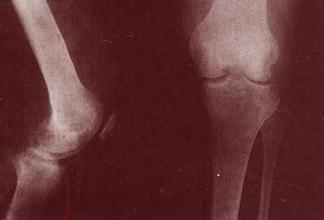

色素绒毛结节性滑膜炎没有明显的全身症状,患者体温不高,血沉不快,血象也无改变。局部症状在早期也较轻微,因此患者就诊较晚,病期较长,一般病期以1-5年者较多,半数以上有外伤史。其主要症状为关节肿胀,疼痛多比较轻微,局部皮温有时稍高,关节功能受限多不明显。呈弥漫性肿胀的关节,触及增厚的滑膜呈海绵样感觉,积液多的可触及波动感。有时可触到大小不等并稍能移动的结节。 》》》有疑问?没看明白?可点击【在线医师】咨询

膝关节受累时髌上囊及髌骨肿胀明显,积液多的浮髌试验阳性。增生的滑膜组织有时可穿破后关节囊而进入腘窝,并沿小腿后方肌间隙向下蔓延,产生深在的弥漫性肿胀。踝关节受累者肿胀在内、外踝周围较明显。髋关节受累时肿胀多位于髋关节前方。 >>>点击此处,专家一对一为您详解滑膜炎